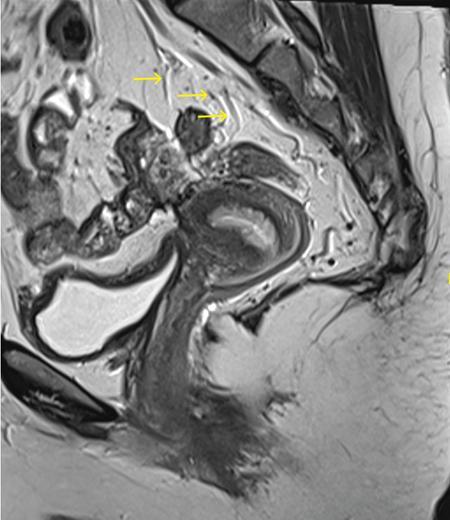

Sumit Mukhopadhyay, Saugata Sen, Aditi Chandra, Argha Chatterjee, Priya Ghosh, Anisha Gehani Cloaca is the part of hindgut caudal to the attachment of the allantoic diverticulum. It divides into a broad anterior urogenital (vesicourethral and urogenital sinus) part and a narrow posterior anorectal compartment/primitive rectum, separated by the urorectal septum. This anorectal compartment gives rise to mid rectum and lower rectum and upper part of anal canal proximal to dentate line. The peritonealized upper part of rectum develops from hindgut proximal to cloaca. The distal most part of anal canal below the dentate line develops from invaginated ectoderm known as proctodeum (Fig. 8.5.1). Initially during development, the rectum is suspended from the posterior abdominal wall by a mesentery, along with the rest of the gut. After completion of rotation of the gut, rectal mesentery fuses with the posterior abdominal wall, majority of rectum becomes retroperitoneal and hindgut mesentery is seen as mesorectum. The artery of the hindgut is inferior mesenteric artery. Anatomically, classically taken as 6 inches (approximately 15 cm), or beginning at the level of S3 vertebra. Surgically defined as 15–18 cm from anal verge (AV), thus anal canal and rectum are considered together for the purpose of surgical and radiological anatomy, though management differs in cases of rectal adenocarcinoma and anal squamous cell carcinoma (SCC). Various trials on rectal cancer neoadjuvant therapy have taken different lengths of cut-off for rectal cancer starting from AV: 9 cm, 12 cm, 15 cm or 16 cm (Table 8.5.1). Rectum continues as sigmoid colon superiorly. The point of transition between rectum and sigmoid colon is controversial. Anatomically, this is the point where sigmoid mesocolon ends, appendices epiploicae are lost and taenia coli gradually converge and disappear. There is no single transition point between these features. These features are not visible to the radiologist/endoscopist as well. Several features defining rectosigmoid junction/transition are variously accepted by different radiologists: Rectum continues as anal canal, which opens to the exterior at AV (mucocutaneous junction). Anorectal junction (ARJ) is considered to be the point at which the angle of the long axis changes, and corresponds to the upper border of puborectalis muscle. The change in axis of anal canal and rectum is well visualized on sagittal MRI. Dentate line lies along the anal crypts (the openings of anal glands), and vertical folds called columns of Morgagni extend superiorly from the dentate line. Anatomists consider the dentate line to be the landmark for ARJ, but the dentate line lies distal to the puborectal sling, and this definition is not clinically relevant. Anal canal is directed posteroinferiorly. At ARJ, the long axis of rectum changes so that it is directed anteroinferiorly. Mid rectum and upper rectum follow the sacral concavity, and the long axis of rectum is again directed posteroinferiorly. Upper rectum is frequently mobile and may not be in midline. Three incomplete folds consisting of mucosa, submucosa and circular muscles, named as Valves of Houston, are seen within the lumen of rectum during endoscopy, but these are not visualized radiologically. The middle valve is roughly at the level of anterior peritoneal reflection, and the superior most valve is at the level of rectosigmoid junction. Surgically and radiologically, rectum is divided into thirds: lower third, middle third and upper third (Table 8.5.2). Most commonly, this division is according to distance or length from AV. Lower third is 0–5 cm, middle third is 5–10 cm, upper third is 10–15 cm from AV (Fig. 8.5.6). Some radiologists define low rectum as 6 cm or less from AV, mid rectum as 7–11 cm and upper rectum as 12–15 cm. The justification of defining low rectum as 6 cm or less from the AV is that, management of most of the tumours at this location suffers from surgical challenges due to tapering of mesorectum and proximity of other pelvic structures. These tumours have a higher rate of CRM positivity, abdomino-perineal resection (APR) and permanent stoma, higher rates of recurrence and mortality, poor function of stoma after sphincter preservation. Another way of defining low rectum, surgical management of which differs from the upper two-thirds, is the portion lying distal to the proximal origin of levators at pelvic side wall. This definition was provided by the English National Low Rectal Cancer Development Programme (LOREC) and is best visualized in the coronal plane by a line joining proximal origins of levators at pelvic side walls (Fig. 8.5.7). ARJ is an important landmark in the management of rectal cancer. Distance between lower border of the tumour and ARJ is important for treatment planning. ARJ is defined as the point at which puborectalis fuses with the levator muscles, and the long axis of rectum changes from anteroinferior to posteroinferior at this point. Its upper extent begins few centimetres above the dentate line, and its length varies from 2–5 cm from AV. Histologically the proximal end of the anal canal is the point at which the columnar epithelium of the rectum becomes the transitional epithelium. Anal canal mucosa has several longitudinal columns, known as anal columns, which end at the dentate line. Below the dentate line the mucosa is smooth and transitions into skin at AV. Approximately at the level of dentate line, the internal anal sphincter (IAS) ends, and the smooth mucosa leads to the intersphincteric plane, distal to which the external anal sphincter extends up to the AV (Fig. 8.5.8). Upper third of rectum is anteriorly covered by peritoneum. Peritoneal covering gradually widens superiorly till it is covered by peritoneum on all sides at the level of sigmoid colon. The exact level of peritoneal reflection varies between individuals, and is quite often seen in axial and sagittal MRI. In axial T2-weighted MRI, a thin hypointense layer with V-shaped attachment to anterior rectal wall is seen representing the anterior peritoneal reflection. This is known as the ‘sea-gull’ sign. Mesorectum and mesorectal fascia (Fig. 8.5.10): lower two-thirds are surrounded by extraperitoneal fat and connective tissue known as mesorectum, which contains lymph nodes, nerves and blood vessels (descending branches of superior rectal artery and corresponding veins). Mesorectal fat is contained within a thin layer of fascia, known as mesorectal fascia (MRF). MRF separates mesorectal fat from extra mesorectal tissues of the pelvis. A relatively avascular plane of areolar tissue lies between MRF and parietal pelvic fascia, facilitating surgery. Importance: Assessment of structures within mesorectum is important for staging and prognostication of rectal cancer. Mesorectal node involvement is N disease. Tumour extension within mesorectal vessels is known as extramural vascular invasion (EMVI) and is thought to be associated with higher chances of vascular dissemination and distant metastases. MRF forms the boundary of the surgical excision plane in total mesorectal excision (TME) – the standard surgery for rectal cancers at present. It is important to understand the various fascial reflections of the pelvis in order to understand pathways of disease spread. The plane between the MRF and the pelvic fascias is the surgical plane. Posteriorly, covering the sacrum, presacral venous plexus and hypogastric nerves, lies the presacral fascia. It fuses with MRF inferiorly at the level of levator ani muscle. The space between presacral fascia and MRF is known as the retrorectal/rectosacral/pelvirectal space, and that between the sacrum and presacral fascia is the presacral space. The presacral fascia continues laterally as the parietal pelvic fascia which covers the lateral pelvic wall. It has two lamellae which encase the pelvic visceral nerves as they course forward from the sacrum to the anterior pelvic organs. The rectosacral fascia/Waldeyer fascia, called as rectosacral ligament by anatomists, is a thickening arising from presacral fascia and running forward to meet the MRF. This divides the rectosacral space into a superior and an inferior compartment, communicating with each other. In males, anteriorly, between the rectum and prostate-seminal vesicles, lies the rectoprostatic fascia/Denonvillier fascia. It is difficult to distinguish from the closely related MRF, and carries the hypogastric nerve and vascular branches to the prostate and male genital organs. In females, anterior to the MRF, lies the rectovaginal septum. According to most views, this septum consists of two layers. The anterior layer corresponds to Denonvillier fascia, and extends from the pelvic floor to the posterior wall of vagina and uterus. The posterior layer is in close relation to the MRF, runs from the pelvic diaphragm and ascends to the peritoneal reflection before fusing with the rectal wall. The lateral rectal ligaments are controversial structures as they are not visualized by imaging and may not carry important structures such as nerves and vessels. However, in some cases, the middle rectal artery may run through them and the accompanying lymphatics may provide a pathway between mesorectal and extra mesorectal lymph nodes. In females, the pelvic floor may be considered to have three compartments, anterior compartment containing bladder and urethra, middle compartment containing the vagina and the posterior compartment containing the rectum. These compartments are supported by the endopelvic fascia and levator ani muscle. The levator ani has several compartments, of which the two most important ones are the iliococcygeus and puborectalis. The iliococcygeus starts as the same fibres as the EAS, and then fans out as a sheet to insert at the pelvic sidewall at the tendinous arch. Posteriorly these fibres fuse in the midline to form the levator plate/raphe. The pubococcygeus and puborectalis are considered together as pubovisceralis muscle. It inserts lateral to the symphysis pubis anteriorly, and forms a sling around the rectum, pulling it anteriorly. Components of the levator ani can be identified in T2-weighted MR images. In males, there are two compartments, anterior containing bladder, urethra, prostate and seminal vesicles and the posterior compartment containing the rectum. Pubococcygeus consists of pubourethralis and puborectalis in males. In sagittal images, the pubococcygeal line is an important reference line, drawn from the inferior border of symphysis pubis to the last joint of the coccyx, representing the level of pelvic floor. The H line is drawn from the inferior aspect of the symphysis pubis to the posterior wall of the rectum at the level of ARJ. This represents the anteroposterior width of the levator hiatus, and upper limit of normal is 5 cm. The M line is the vertical descent of the levator hiatus, drawn as a perpendicular line dropped from the pubococcygeal line to the posteriormost aspect of the H line, and should measure maximum 2 cm. The angle of the levator plate and the pubococcygeal line is also measured. In axial images, the entire normal levator is of uniform thickness and homogeneous low signal intensity. Coronal images show intact iliococcygeus muscle which is convex upwards. The upper half of the anal canal proximal to the pectinate line, the IAS, the conjoint longitudinal coat and the rectum drain lymph upwards into the mesorectal nodes (Fig. 8.5.11) and then lymphatics follow the superior rectal artery into the inferior mesenteric group of lymph nodes. The lymph from these nodes is carried by the intestinal lymph trunk(s). Anal canal below the dentate line along with the EAS drains to the superficial inguinal nodes. Lymphatic vessels also travel with the median sacral artery and drain the puborectalis muscle before finally joining the internal iliac lymph nodes. The internal iliac lymph nodes drain into pre-aortic and paraaortic (lumbar) lymph nodes and efferents from the nodes form the lumbar trunks. The intestinal trunks and the lumbar trunks enter the abdominal confluence of the lymph trunks at the level of the L1–L2 vertebrae, called the cisterna chyli, and then ascend as the thoracic duct. The pelvic lymph nodes lying outside the mesorectum are termed as ‘extra mesorectal lymph nodes’. Above the dentate line: blood supply is from the superior rectal artery, which originates from the inferior mesenteric artery, a branch of abdominal aorta. Superior rectal artery passes in the sigmoid mesocolon and divides into two branches behind the rectum at the level of S3 sacral segment. The superior rectal artery ends in the anal columns by forming a rich vascular plexus/anastomosis with the branches of inferior rectal artery. Blood returns via the superior rectal veins into the inferior mesenteric vein, which drains into the splenic vein and eventually into the portal venous system. Below the dentate line, the inferior anal canal obtains its blood supply from the inferior rectal artery, which is a branch of internal pudendal artery, originating from the anterior division of internal iliac artery. Blood returns via the inferior rectal vein, which drains into internal pudendal veins, internal iliac veins and ultimately into the inferior vena cava (systemic circulation). Thus anal canal is a site of portosystemic anastomosis. Due to the venous anastomoses that occur in the anal canal and the backup of blood flow into the rectal veins, haemorrhoids may be present in patients with portal hypertension. A small part of muscular wall of rectum and anal canal is also supplied by median sacral artery, a direct branch of abdominal aorta arising at the bifurcation of aorta. Nerve supply: The inferior hypogastric plexus lies laterally on the surface of MRF on both sides. It receives sympathetic nerve fibres from the superior hypogastric nerves and parasympathetic ‘nervi erigentes’ from the laterally situated sacral nerves (S2–S4). Laterally, inferior rectal branches of the pudendal nerves and internal pudendal arteries cross the ischio-anal fossa to supply the external sphincter and anal mucosa. T2-weighted small FOV images reveal the layers of rectal wall and details of perirectal soft tissue and pelvic floor most accurately. For adequate assessment of the integrity and involvement of different layers, axial images are needed, which should be obtained perpendicular to the axis of the rectum in that segment. Angle of acquisition should be altered according to the change in axis of rectum (Fig. 8.5.12). The layers of rectal wall from inside to outside are (Fig. 8.5.10): When examining the anorectum with a radial scanning echoendoscope, the internal and EASs can be seen as two distinct rings. The inner hypoechoic ring of tissue represents the IAS the outer hyperechoic tissue ring represents the EAS. The thickness of normal IAS is 2–3 mm, and for EAS: 7–9 mm. The IAS becomes thicker and more hyperechoic with age, while the EAS tends to become thinner with age. Endoscopically, rectum begins at the dentate line and extends to 15–20 cm from the AV. The normal five-layer appearance of rectal wall in EUS is as follows: Imaging in the rectum and anal canal region is mainly for staging of tumours. The most common neoplasm of this region is rectal cancer and preoperative imaging evaluation is required not only for staging early and advanced disease but also for assessing response to treatment and for surgical planning. The techniques described here will mainly pertain to rectal and anal neoplasms. Plain radiographs have a limited role in the evaluation of rectal neoplasms. Primarily, it may be used as a modality in the emergency setting when patients come with constricting colorectal strictures causing large bowel obstruction. Radiographs of the abdomen in supine and erect positions are performed to look for features of bowel obstruction, air-fluid levels and free air under the domes of diaphragm in case of perforation, respectively. Conventional luminal contrast study is now obsolete for diagnosis of tumours in the rectum and anal canal and have been replaced by cross-sectional imaging. Sinogram studies with diluted iodinated contrast have been performed to detect extent of rectal fistulae. Endorectal Ultrasound (ERUS) can differentiate between the layers of the rectal wall and helps detect and stage tumours within the different layers of the rectum. ERUS can view the rectal mucosa in 360 degrees. The layers visualized include rectal mucosa, muscularis mucosa, submucosa, muscularis propria and area between the muscularis propria and perirectal fat. The role of ERUS in rectum is primarily in staging and in posttreatment surveillance of rectal adenocarcinoma. Staging of early tumours requires an ERUS due to its superior diagnostic performance for differentiating T1 from T2 tumours in comparison to other cross-sectional imaging modalities like MRI. As far as surveillance is concerned, endoscopy is mandated as it can detect early asymptomatic recurrences which improves overall survival (OS). This is substantiated by multiple recent meta-analyses in literature. Hence, even for patients on ‘watchful waiting’ as a treatment option after chemoradiotherapy, it is imperative to perform a DRE, EUS, CEA and correlate the findings with restaging MRI. The various recommendations for postoperative surveillance for rectal cancer using endoscopy are enumerated in Table 8.5.3. ASCO: American society of clinical oncology; ESMO: European society for medical oncology; NCCN: National comprehensive cancer network; USMSTF: United States Multi-Society Task Force. Drawbacks include heterogeneity in operator skill and operator dependency as well as inability to pass stenosing lesions. Poor depth of penetration of the probe results in reduced visualization of the mesorectal fat, limited assessment of pelvic side walls and EMVI and reduced diagnostic accuracy for asserting involvement of CRM. Multidetector CT (MDCT) is the primary imaging modality used for rapid evaluation of not only bowel pathologies (luminal or mural) but also for evaluation of surrounding structures such as vessels, lymph nodes and mesentery. The ability to obtain high-quality clinical images through multiplanar reconstructions make it one of the most robust examinations for the initial evaluation of most bowel related pathologies. A routine abdominal CT scan would include acquiring a noncontrast axial image, followed by a portal phase image (at 70–90 seconds). However, for more detailed evaluation of solid organs, a general imaging dataset would include an unenhanced CT, followed by arterial phase (20–30 seconds), portal venous phase (70–90 seconds) and a delayed phase at 3 minutes. Many centres around the world omit the noncontrast scan to reduce radiation exposure. Lesions such as large tumours, pelvic nodes, collections and diverticulosis can be detected by contrast-enhanced CT. CT provides a more holistic evaluation and demonstrates possible complications of tumours such as obstruction, transition point and perforation that may not be clinically evident. However, accurate detection and staging of tumours in the rectum is better performed by MRI. Like TRUS, MRI can depict the layers of the rectal wall with high resolution, especially when performed at 3 Tesla and with an endorectal coil. Although use of endorectal coils may provide improved diagnostic accuracy for T stage as compared with phased-array coils alone, it is known that endorectal coils increase patient discomfort and may account for increasing motion artifacts. Insertion of such coils is also not possible in case of stricturous lesions. Performance of high-resolution imaging using phased-array MRI coils at 1.5 or 3 Tesla, as was used in multicentre trials was excellent. MRI technique and image quality play a critical role in evaluation of rectal cancers, and accuracy is dependent on obtaining high-resolution images that are perpendicular to the plane of the tumour. Particular note is to be made whether the tumour is mucinous or nonmucinous as the former have worse prognosis and higher tendency to metastasize. For technical aspects of MRI, it is recommended by ESGAR that bowels and bladder are emptied. Rectal distension is not indicated as it stretches out the CRM. Minimum slice thickness for such scans is 3 mm. DWI is essential for both primary staging and restaging. Microenemas may be considered to remove air from the rectum and reduce artifacts in DXI sequence. High-risk MRI features for distant metastases include EMVI, mesorectal tumour depth >5 mm, T4 stage, involved circumferential resection margin (CRM). In addition to initial staging prognostic features, MRI also helps in assessing response to neoadjuvant therapy which is also an indicator of survival and chances of recurrence. MRI is sensitive in detecting the presence of lymph nodes but remains nonspecific for differentiation malignant from benign nodes with high diagnostic certainty owing to the presence of micrometastasis even in small-sized nodes (up to 5 mm). Contrast administration is not recommended. Drawbacks of MRI include reduced diagnostic accuracy for identifying early rectal T1 and T2 tumours, and to sometimes differentiate T2 from early T3 lesions. Increased scan times in the elderly and cost may also be constraints in some settings. Virtual colonoscopy can help in identifying primary and synchronous colonic lesions. CT Colonography (CTC) is beneficial after incomplete colonoscopy (due to nonpassable stricture) to evaluate the remainder of the colon. CTC is advocated as a screening test for colonic polyps and colon cancer in vulnerable populations. It has a sensitivity of 93% and a specificity of 97% for detecting polyps >1 cm. MRI scores over all modalities in the local staging of rectal neoplasms. The more common application of PET-CT is in identifying nodal and distant metastases in rectal adenocarcinoma, melanoma and lymphoma. Limitations of PET include poor sensitivity in detecting small (<10 mm) colonic lesions and decreased fluorine-18-2-fluoro-2-deoxy-D-glucose uptake by mucinous tumours. For rectal melanoma, MRI may be performed along with a whole body PET-CT scan for regional and overall staging. Rectal lymphoma does not require local staging and a whole body PET-CT is generally acceptable as the imaging modality of choice. MRI is the imaging modality of choice due to better delineation of the extent and involvement of the anal sphincters. The inguinal nodes are regional nodes in anal cancer and this region is covered in the scan. The most common rectal tumour is rectal cancer. It is also one of the most common malignant neoplasms and the second most frequent cancer occurring in the large bowel. Majority of the patients are in the fifth to seventh decade. However, the incidence of rectal cancer has been on a rise in the younger population. Adenocarcinoma is the commonest histopathologic type of rectal cancer. Other than adenocarcinoma, several other neoplastic lesions also occur in the rectum, but are relatively uncommon (Table 8.5.4). Diagnosis of rectal cancer begins with physical examination/DRE followed by colonoscopy/sigmoidoscopy and biopsy from the mass (see figure below). If malignancy is confirmed on histopathological examination, imaging for staging is ordered (Fig. 8.5.14). MRI is the preferred method for locoregional staging. During staging of early tumours, ERUS also plays an important role. Majority of the guidelines (SAR and ESGAR) accept MRI as the modality of choice for locoregional staging and restaging after neoadjuvant treatment. CT thorax and abdomen is performed for metastatic evaluation. PET-CT is not routinely recommended in metastatic evaluation. ESMO guidelines outline the following indications for PET-CT: (1) If carcino-embryonic antigen (CEA) is high on presentation (2) Extensive EMVI. MRI of the liver may be recommended to evaluate any suspicious or equivocal lesions that are detected on CT scan. Therefore routinely pelvic MRI for locoregional evaluation and CT thorax and abdomen for metastatic evaluation is performed (Table 8.5.5). Based on the investigations, the rectal cancer is staged according to the latest AJCC classification (Table 8.5.6). T0 No evidence of primary tumour Tis Carcinoma in situ T1 Tumour invades submucosa T2 Tumour invades muscularis propria T3 a b c d Tumour invades subserosal tissue and perirectal tissue a <1 mm b 1–5 mm c >5–15 mm d >15 mm T4 a b Tumour invades peritoneum or other organs Tumour penetrates visceral peritoneum Tumour invades other adjacent organs or structures NX Regional lymph nodes cannot be assessed N0 No regional lymph node metastasis N1 a b c Regional lymph node metastasis (1–3 nodes) 1 lymph node 2–3 lymph nodes Tumour deposits in subserosa, mesentery/nonperitonealized perirectal tissues (cannot be differentiated from nodes on imaging) N2 a b Regional lymph node metastasis (>4 nodes) 4–6 node >7 nodes M0 No distant metastasis M1 a B c Distant metastasis Metastasis in one (1) organ Metastasis in more than one organ Metastasis to the peritoneum with/without other organ involvement Once the diagnosis is confirmed and staging investigations are completed, management is usually decided in multidisciplinary team meetings consisting of Surgeon, Radiation oncologist, Medical oncologist, Pathologist and Radiologist. The treatment protocols differ in the United States and Europe (Fig. 8.5.15). The different types of rectal surgeries are enumerated in the Table 8.5.7 and depicted in Fig. 8.5.16. Concept of use of neoadjuvant short course RT, long course RT with chemotherapy and chemotherapy only is a rapidly evolving field. Radiologist should be aware of the protocol used in their institution. A subset of patients (10%–23%) was found to have complete pathological response (pCR) in the postsurgical pathological specimen. There is significant evidence of prediction of pCR on presurgical MRI. Considering the ability of MRI in prediction of pCR, Prof. Habr-Gama and her group suggested the possibility of organ preservation in these patients. Hence ‘watch and wait’ policy came into vogue. In the subgroup where MRI predicts complete response, surgery can be avoided and patients may be followed up every 8–12 weeks using DRE, proctoscopy/sigmoidoscopy and MRI. Both T2W and DWI are used in MRI for prediction of complete response as well as for follow-up for prediction of recurrence. Close follow using the above-mentioned protocol ensures early detection of recurrence and hence treatment. Thus, MRI plays an important role in personalized treatment of rectal cancer. MRI plays an important role in rectal cancer management: During initial staging MRI helps in: In restaging after NACT, MRI helps in: Therefore good-quality high-resolution rectal MRI is required for accurate locoregional staging. Technique and protocol of MRI is summarized in the Tables 8.5.8 and 8.5.9. 1.5T-3.0T magnet strength High resolution T2w sequences Small FOV images Axial and coronal images – parallel and perpendicular to the rectal tumour For low rectal tumours coronal images –perpendicular to the anal canal

MRI anatomy